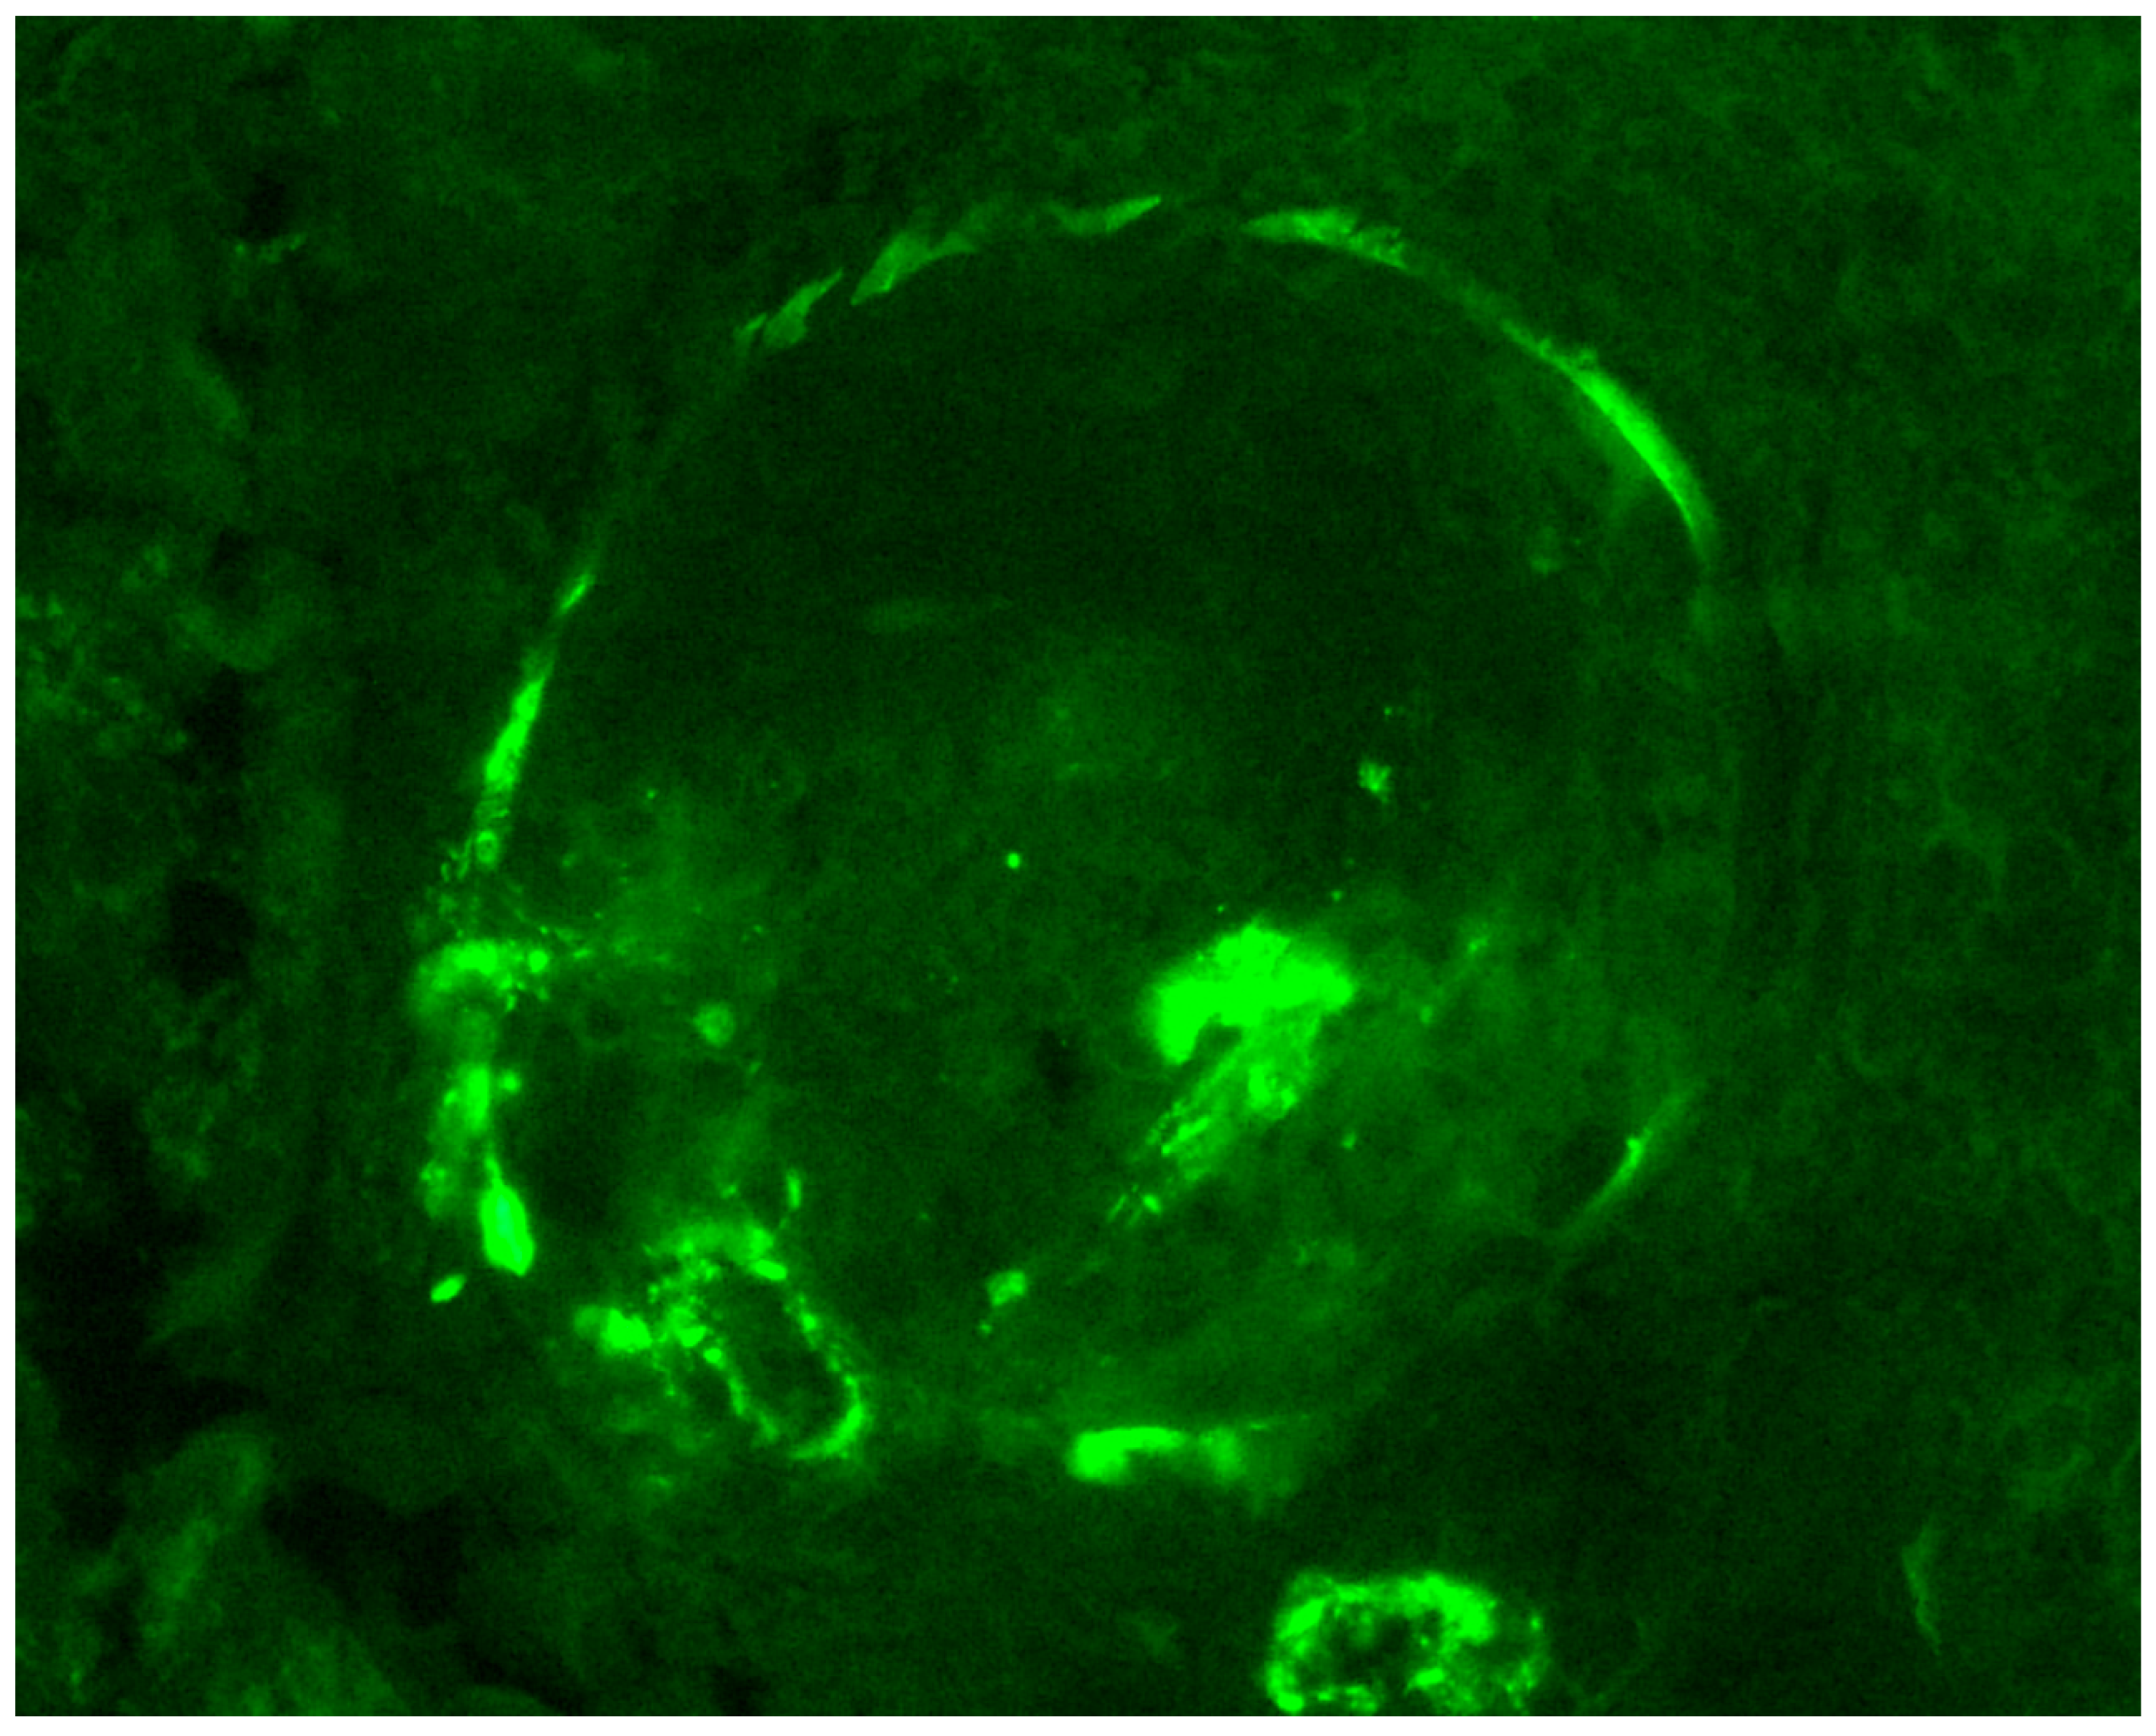

- Hakroush, S.; Tampe, D.; Baier, E.; Kluge, I.A.; Ströbel, P.; Tampe, B. Intrarenal synthesis of complement C3 localized to distinct vascular compartments in ANCA- associated renal vasculitis. J. Autoimmun. 2022, 133, 102924. [Google Scholar] [CrossRef]